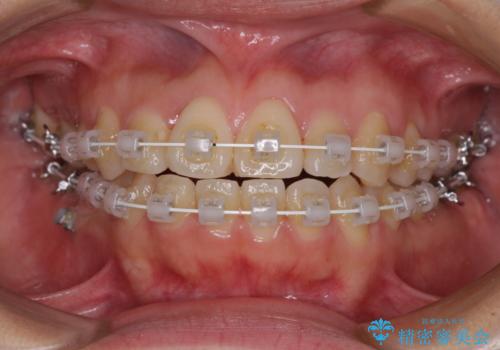

受け口傾向の非抜歯矯正であったため、インビザラインによる矯正治療をお勧めしましたが、自己管理が面倒であるとのことで、ワイヤー装置にて行うこととしました。

なお、右奥の歯が180度回転した状態で萌出しており、こちらは改善困難なため、そのままの向きで配列することとしました。

右奥の歯が180度回転していることで、噛む度にワイヤーに無理な力がかかったようで、頻繁にワイヤーが切れてしまいました。また、下顎を後方に移動させるためのアンカースクリューも脱離することが多く、治療期間が長くなってしまいました。